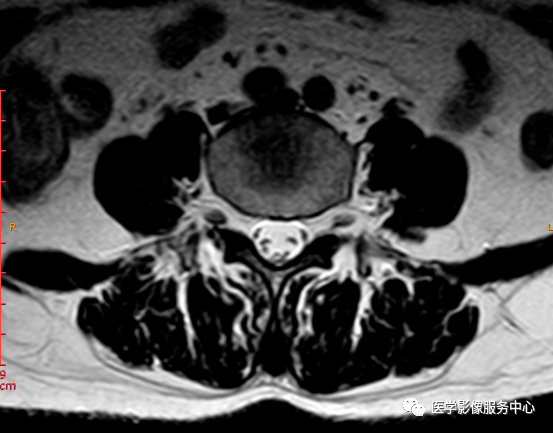

T2轴位

这个患者腰椎间盘膨出程度不明显,神经根没有明显的受压,椎管未见明显狭窄,那这个患者腰疼的“罪魁祸首”是腰椎间盘膨出嘛?

L3-4椎间盘后缘可见点状高信号区(红色箭头所指处)

红色箭头所指的异常信号区是是什么呢?平时工作中大家有没有遇到这种情况,你会不会忽略这个异常信号?有没有想过这个椎间盘后缘高信号区是引起患者腰疼的重要因素呢?下面为大家重点介绍。

影像表现主要在T2矢状位及T2横断位可见椎间盘前缘或后缘可见高信号区;